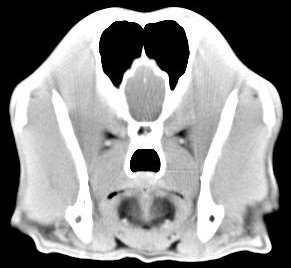

imágenes de TC en el perro | ||||||||||

ejemplo de imágenes de TC en el perro. Nótese la celulitis en la región parotídea izquierda | ||||||||||